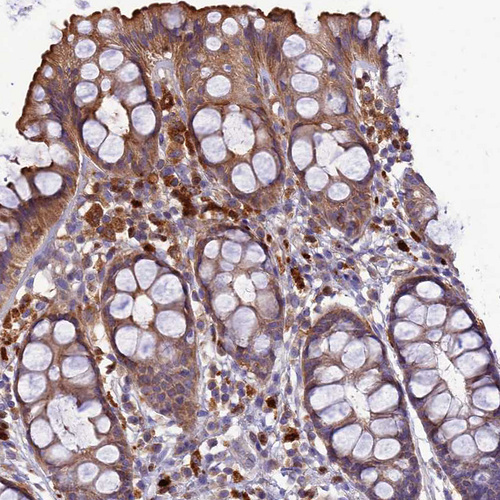

Immunohistochemical staining of human lung shows strong cytoplasmic positivity in macrophages.